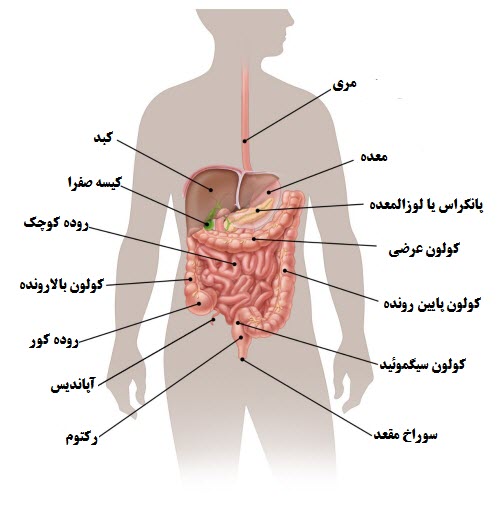

عکس داخل شکم انسان. در این همان طور که مشخص است شکم حالت بیضی شکل پیداکرده و این بیضی که کناره های شکم کشیده شده است. تعداد سلول های بدن انسان حدود ۳۷ ۲ تریلیون تخمین زده شده اند. Abdomen که در زبان عامه به غلط به آن دل نیز می گویند در آناتومی به قسمتی از تنه گفته می شود که مابین دیافراگم از بالا و سطح فوقانی لگن خاصره از پایین قرار دارد. ربات دیدنی ربات انساننمای چینی به صورت یک دختر جوان ساخته شده و جیا جیا نامگذاری شده است این ربات طوری برنامهریزی شده که میتواند صحبت کند و احساسات خود را از طریق تغییرات در چهره حالات.

شکل دوم شکم مادری را نشان می دهد که جنین دختر دارد. وحشت مادر از عکس سونوگرافی جنین داخل شکمش عکس. تصاویر جالب از داخل مغز و نخاع انسان آخرین نیوز. بدن انسان کل ساختار انسان است که سر گردن تنه سینه و شکم دو بازو و دست ها و دو ساق پا و پاها را شامل می شود.